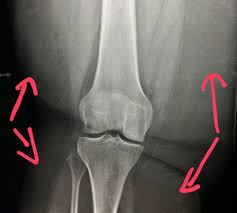

The patella or kneecap is seen sitting in front and to the left of the femur. A lateral view x ray shows the knee from the side. The image here is a front to back view of the knee joint also called the ap view.

Find x ray of knee stock images in hd and millions of other royalty free stock photos illustrations and vectors in the shutterstock collection. Add to likebox 127713977 wheelchair icon simple style. X ray image of right knee ap and lateral view showing total knee arthroplasty and fractures of the tibial plateau with. This x ray shows a healthy joint with nice sharp well defined edges at the joint margins.